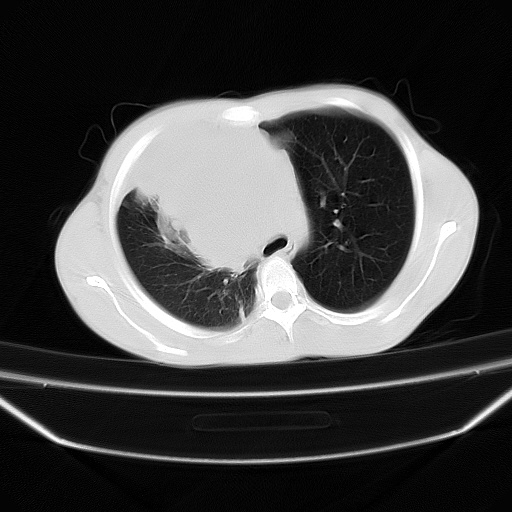

以下是引用zjzjr在2008-7-20 12:57:00的发言:[br]考虑为生殖源性肿瘤(内胚窦瘤),侵袭性胸腺瘤可能性大;右侧少量胸腔积液。

以下是引用xinliheng001在2008-7-20 21:17:00的发言:[br]右纵隔巨大分叶状软组织均质密度肿块,右上肺叶受压明显,纵隔右移、胸膜受累有少量积液和结节样增厚。应增强扫描一定会有更具诊断价值的信息。

以下是引用xinliheng001在2008-7-20 21:17:00的发言:[br]右纵隔巨大分叶状软组织均质密度肿块,右上肺叶受压明显,纵隔右移、胸膜受累有少量积液和结节样增厚。应增强扫描一定会有更具诊断价值的信息。